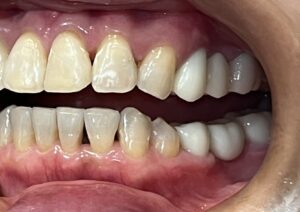

本日は、ジルコニアセラミック(歯科用人工ダイヤモンド)を使用した

メタルフリー治療の症例をご紹介いたします。

治療前は、メタルの詰め物が多数入っておりましたが、

患者様より詰め物を白くキレイにしたいとのことで治療を行いました。

Before After

メタルフリーになり、お口の印象がとても明るくなりました!

メタルフリー治療を行うと、審美的な改善が大きいですが

それだけではありません!

詰め物、被せ物にジルコニアセラミックを使用することで

経年的な摩耗や変色を最小限に抑える、

金属アレルギーのリスクがない、

歯質との適合性が高く、むし歯の再発リスクが低いなど、様々なメリットがあります。

前歯のレイヤリングジルコニアは特に色味や形態をぴったり合わせるため、

セラミストが写真撮影、デジタルトライインを行って作成します。

笑顔がさらに素敵になりましたね✨

患者様にも、とても喜んでいただけました😊